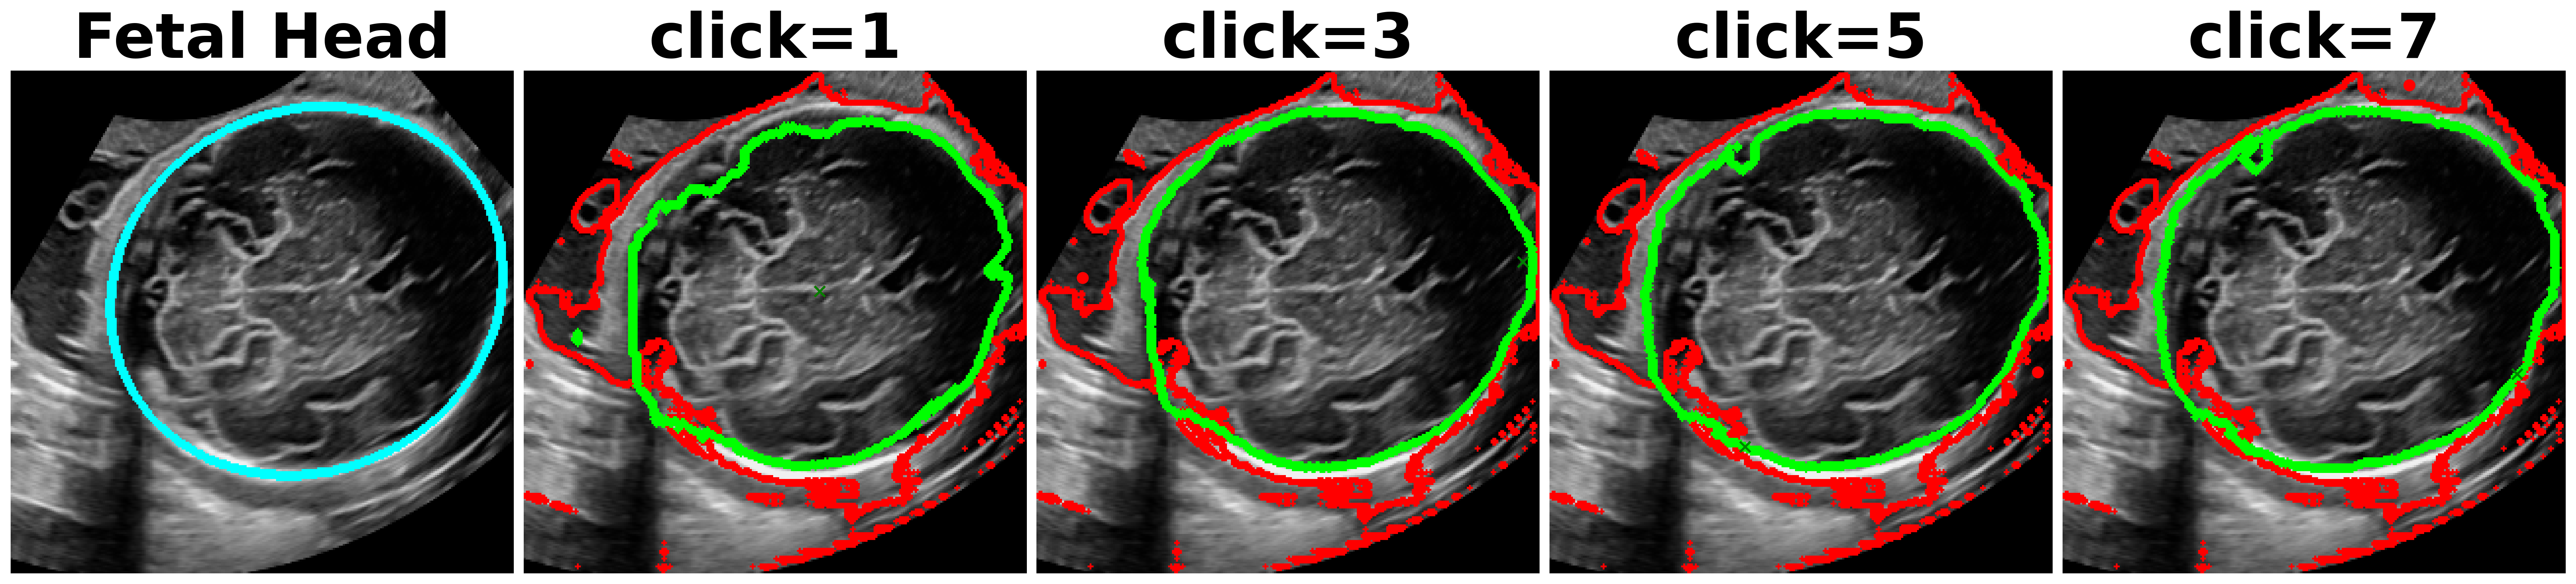

Utility of SAM[3] in medical imaging has been assessed recently in [27, 28, 29]. In an extensive experimental study [27], the authors find that while SAM obtains reasonable performance on different modalities, the performance is the poorest on ultrasound. This behavior is to be expected since ultrasound possesses unique characteristics like presence of scan cone, poor image quality and unique texture with speckles. Fig. 1a shows inefficiency of SAM and other methods on different anatomies, where after each click, our method outperforms consistently all the other methods.

SonoSAM achieves DSC on all data-sets and comfortably surpasses competing methods by a huge margin which struggle to cross even DSC. As shown in Table. 2, SAM model trained on natural images, under-performs significantly on ultrasound images often being poorer than SonoSAM in range of MaxDSC. Surprisingly, MedSAM which has been trained partly on ultrasound images is often the worst performer amongst all models, despite 3 of these datasets being ‘in-domain’ data-sets for MedSAM. Lack of training with clicks, severely hampers and infact deteriorates MedSAM’s performance. FocalClick model, performs reasonably on two data-sets - Liver and Fetal Head but takes several clicks to get to meaningful results, as shown Figure 7

One of the complaints with SAM model is that, the mask generated with user clicks (positive or negative clicks) are unintuitive and unpredictable. As shown in Figure 8, SAM often picks the entire FOV as the object and is unresponsive to multiple clicks. In contrast, SonoSAM’s responses are predictable, as demonstrated by smooth progression of predicted contours as shown in Figure 8